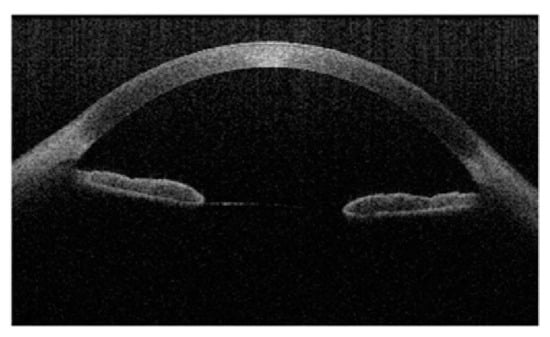

3.3. Anterior Segment Optical Coherence Tomography (AS-OCT)

- Li, J.; Zhang, H.; Wang, X.; Wang, H.; Hao, J.; Bai, G. Inpainting Saturation Artifact in Anterior Segment Optical Coherence Tomography. Sensors 2023, 23, 9439. [Google Scholar] [CrossRef] [PubMed]

- Macias, B.R.; Patel, N.B.; Gibson, C.R.; Samuels, B.C.; Laurie, S.S.; Otto, C.; Ferguson, C.R.; Lee, S.M.C.; Ploutz-Snyder, R.; Kramer, L.A.; et al. Association of Long-Duration Spaceflight with Anterior and Posterior Ocular Structure Changes in Astronauts and Their Recovery. JAMA Ophthalmol. 2020, 138, 553–559. [Google Scholar] [CrossRef]